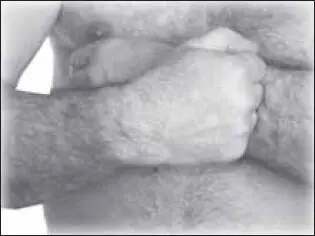

Применяем растирание – прямолинейное (рис. 116), круговое (согнутыми пальцами) (рис. 117).

Затем выполняем поперечное разминание передней поверхности плеча (желательно выполнять движения, передвигаясь снизу вверх) (рис. 118).

Можно использовать разновидности вибрации, например ударные поколачивания всей поверхности плеча (рис. 119). Прием выполняется локтевым краем кисти, сжатой в кулак.